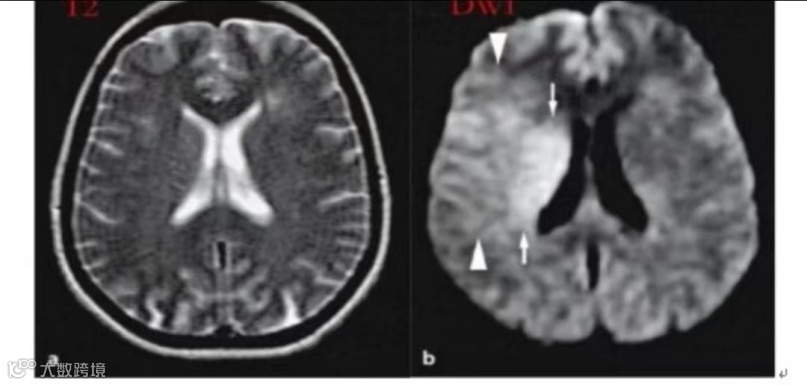

多个序列扫描,更及时、准确发现病变

弥散加权成像DWI:可发现2小时之内的超急性脑梗死,使患者能够早发现早治疗,缩短诊断时间,为医生提供明确诊断;